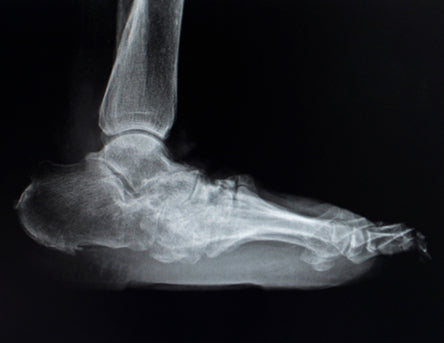

When Your Foot Has a Rocker-bottom Appearance

Charcot foot develops as the result of neuropathy and repeated injury of the foot. There are different stages of Charcot foot, the progression of which takes place over time and worsens with continued walking. The condition can begin with redness and swelling and can eventually result in severe deformity and abnormal rocker shape of the foot.

Over time the foot takes on an abnormal shape, such as a rocker-bottom appearance. The fractures and dislocations can result in severe deformities to the foot and ankle which can include the collapse of the midfoot or instability of the back the foot and the ankle.

If you have Charcot foot it is important to begin treatment with a doctor as early as possible because the foot can be repeatedly worsened by walking. This can result in a rapid progression of the pathology. Early radiographs will show soft tissue swelling and bony fragmentation. Joint dislocation may be seen just several weeks after onset. Make sure to follow a treatment plan from a doctor. Failure to do this can lead to ulcers and possible amputation.